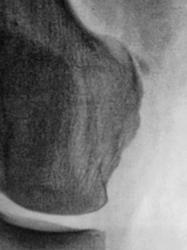

Травма. Пациент направлен на рентгенографию коленного сустава.

Данная картина больше напоминает болезнь Пеллегрини-Штида, обызвествления сухожилия мышцы.

Пеллегрини-Штида

Участок обызвествления у медиального надмыщелка бедренной кости. Возможно оскольчатый перелом.

Костно-травматических изменний не выявлено. Участок линейного обызвествления у медиального надмыщелка бедренной кости - болезнь П.-Ш. (это я сократилаsmiley)